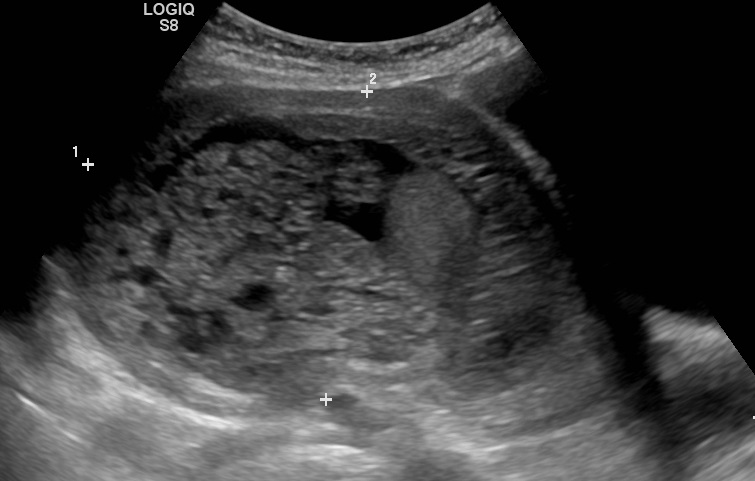

Частичный пузырный занос на УЗИ